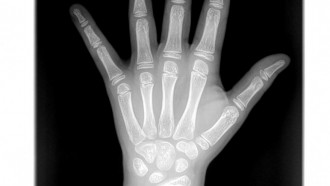

Densytometria jest najlepszą dostępną metodą diagnozowania osteoporozy, również w jej stadium bezobjawowym, czyli przed wystąpieniem złamania kości lub kręgosłupa. Służy także ocenie efektywności prowadzonego leczenia. Jest to rodzaj badania wykorzystującego niewielkie dawki promieniowania rentgenowskiego i ma na celu określenie gęstości mineralnej kości (BMD - Bone Mineral Denstity)

Wyposażyliśmy pracownię w dodatkowy cyfrowy detektor z oprogramowaniem posiadającym funkcję skalometrii (Stitching), dzieki której możliwe jest wykonanie badania telemetrycznego RTG całych kończyn długich i całego kręgosłupa a następnie uzyskanie obrazu diagnostycznego obejmującego razem kilka części anatomicznych połączonych w całość.

MD Multi Diagnostica uruchomiła cyfrowy aparat rentgenowski wyposażony w stół z „pływającym” blatem i zintegrowaną kolumną lampy rentgenowskiej. Jest to solidna niemiecka konstrukcja. Nasz aparat do rentgenodiagnostyki cyfrowej jest aparatem do wszystkich diagnostycznych ekspozycji radiograficznych całego ciała. Wraz ze statywem płucnym pozwala na wykonywanie zdjęć rentgenowskich czaszki, klatki piersiowej (płuc), miednicy oraz kończyn. Generator wraz z lampą RTG wyposażony jest w system AEC (automatycznej kontroli ekspozycji), dzięki czemu dawka promieniowania jest ograniczona do minimum.